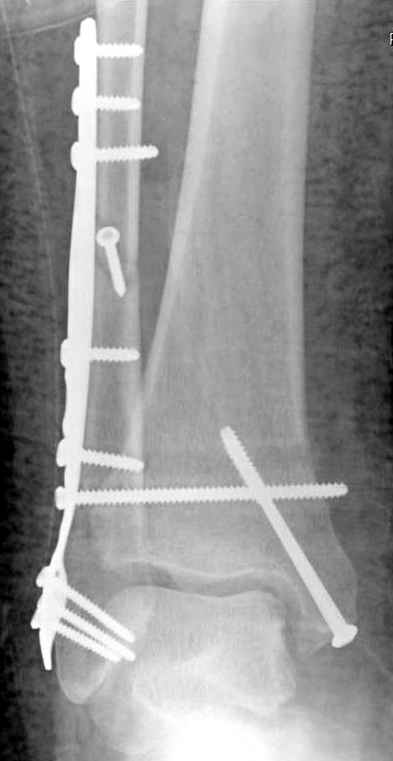

Ниже рентгенограммы

До операции 28 июля

Операция 29 июля

Через месяц

Боковой через месяц

15 ноября прямой

15 ноября боковой

15 ноября трехчетвертной

12 января прямой

12 января боковой

12 января трехчетвертной

Риторический вопрос - в каком руководстве рекомендован такой способ остеосинтеза наружной лодыжки?

Очевидно, такой результат операции был запрограммирован. При невосстановленной длине и практически нефиксированной малоберцовой кости (этот кортикальный винт - как карандаш в стакане), при неустраненном подвывихе, невправленной и тоже нефиксированной внутренней лодыжке нет стабильной вилки сустава. Если такую операцию сделать даже сразу, а не через 4 месяца, то результат ожидаем

тот же.

Вообще говоря, такое повреждение вполне успешно можно лечить без операции - если 6 недель подержать в гипсовом "сапожке" с хорошо устраненным подвывихом. Вероятное несращение внутренней лодыжки не обязательно компрометирует результат.

Ну а уж если выбран остеосинтез - нначать надо было с репозиции малоберцовой кости с точным восстановлением длины, с фиксацией треть-трубчатой пластиной по задней поверхности. Позиционный винт

избыточен - повреждение практически подсиндесмозное. А если бы

действительно было повреждение синдесмоза - в 4 месяца позиционный винт - не решение. Внутренню лодыжку такую - надо было бы спицами и проволочной петлей. Извините за эти банальности.

Вариант с артродезом уже обсудили. Хотя, после увиденых снимков, пессимизм насчет восстановительной операции у меня, например, несколько уменьшился. Особенного уж какого-то остеопороза не видно даже на январских снимках. Можно черед мини-доступы убрать винты, аппаратом вправить малоберцовую кость, устранить подвывих стопы. Ну а дальше фиксировать малоберцовую пластиной сзади. А может, и напряженной Y-спицей попробовать - Анатолий Федорович, как Вы полагаете? Внутреннюю - то, что осталось, если уже не получится сделать спицами и проволокой, то что-то типа пластики дельтовидной связки. А может, и не трогать ее вовсе... В общем, выбор непростой,

много факторов надо взвесить.